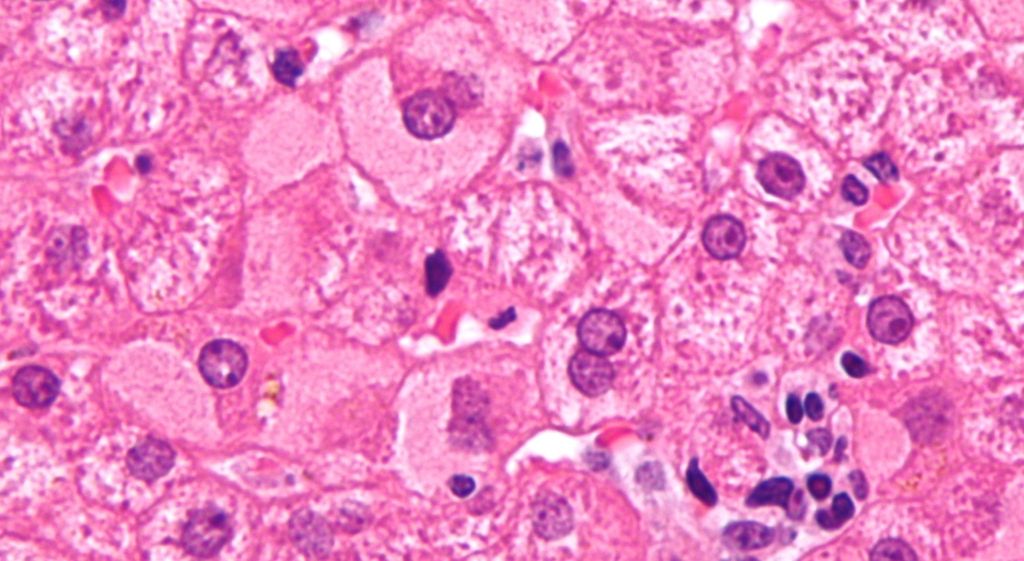

I medici rassicurano: "I numeri sono sopra la media ma non c'è nessuna epidemia". In ogni caso l'impennata di casi di epatite A, concentrata tra Napoli e provincia, continua a suscitare preoccupazione e, soprattutto, a raccomandare prevenzione. I ricoverati nell'ospedale Cotugno, presidio infettivologico di riferimento, sono saliti oggi a 53 rispetto ai 50 di ieri: tutti casi non gravi, ripetono i sanitari insistendo però sull' esigenza di massima attenzione nel rispetto delle raccomandazioni.

Vaccinare i soggetti fragili, è il consiglio degli esperti, e soprattutto evitare assolutamente il consumo di frutti di mare crudi: le ordinanze di divieto nei pubblici esercizi si moltiplicano, da Napoli a Benevento ad Avellino. Di pari passo sono crollati oggi gli acquisti nelle rivendite al dettaglio: la vendita di frutti di mare regolarmente tracciati non è vietata e il consumo del prodotto ben cotto è ritenuto sicuro, ma il virus della preoccupazione è più contagioso di ogni vibrione e quindi pescherie e grande distribuzione lamentano il brusco calo degli acquisti.

I carabinieri del Nas intensificano i controlli e i sequestri dei mitili di cui non è possibile stabilire la provenienza, proibiti in ogni circostanza ma ora ritenuti a maggior ragione pericolosi. Ai frutti di mare crudi, probabilmente consumati durante le feste natalizie considerando la lunga incubazione della malattia, sembra riferita la stragrande maggioranza dei contagi.